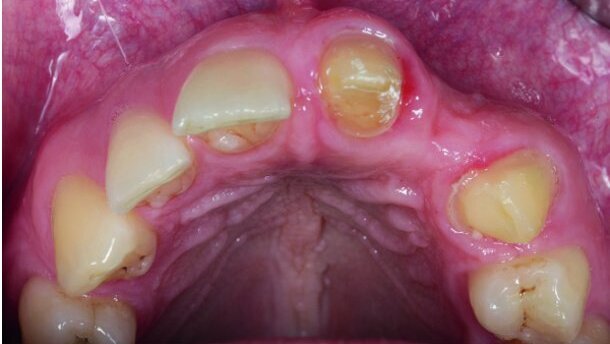

V opisanem kliničnem primeru je načrt protetične rehabilitacije vstavitev zobnega vsadka na mesto manjkajočega stranskega sekalca. To področje je estetsko zahtevno.

Na mestu manjkajočega sekalca je bil prisoten je zmeren vodoraven defekt alveolarnega grebena s širino preostale kostnine 5,6 mm. Postopen pristop je obsegal vodeno kostno regeneracijo z izbrano dodatno svinjsko delno demineralizirano kortikalno lamino (OsteoBiol Soft Cortical Lamina, Tecnoss Dental). Kot polnilni material je bila uporabljena svinjska kostnina (OsteoBiol mp3, Tecnoss Dental).

Po postopku augmentacije alveolarnega grebena, je bila lamina prekrita s kolagensko membrano za hitro integracijo mehkih tkiv. Kirurški postopek augmentacije kosti je bil zaključen z natančno mikro-kirurško tehniko zaprtja režnja.

Po končanem obdobju celjenja je bil po 6 mesecih vstavljen zobni vsadek premera 11mm v skladu z načrtom protetične rehabilitacije. Na koncu je bila cementirana polno keramična prevleka na cirkonijevem oporniku.

S slik po zaključenem zdravljenju je jasno razvidno, da je estetski videz dosežen z opisano tehniko augmentacije kosti.